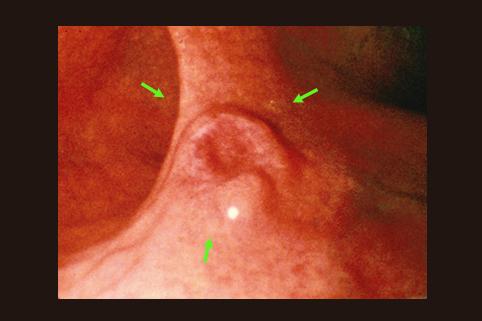

Cáncer Precoz del Estómago, tipo IIa+IIc, crecido en el tercio inferior

[Image-ID:8682]

Tumor Epitelial Maligno/Adenocarcinoma

estómago(región)/cuerpo

Endoscopia

Tipo 0(tipo superficial)/Tipo IIa(IIa+IIc)

15 - 19

sm